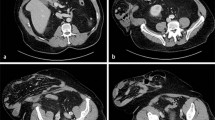

Detailed patient characteristics of TP patients are summarized in Table 2. In only one out of the 15 patients (6.7%), TP was diagnosed non-operatively. In this patient (patient #14), the diagnosis of TP was made 5 days after the IO by clinical signs of infection and laboratory and CT radiographic measurements. In the remaining 14/15 patients (93.3%), TP was diagnosed intra-operatively by relaparotomies after the IO (either first or second relaparotomy; Table 2). As required by the ICU consensus conference definition of TP, these patients showed persistent or recurrent peritonitis ≥48 h following successful and adequate surgical source control which was achieved during IO.2 There was no failure of surgical source control of the IO (e.g., insufficiency of the rectal stump, anastomotic insufficiency, etc.). The median time period between initial operation and diagnosis of TP was 87 h (range 48–338 h).

The mean Mannheim Peritonitis Index, which was recorded at the IO in all patients (n = 69), revealed significant higher values for TP patients (28.6 ± SD 7.0; median 20, range 17–39) compared to SP patients (19.8 ± SD 8.2; median 20, range 4–37; p ≤ 0.001, Mann–Whitney test) as illustrated in Fig. 3. Elevated severity of peritonitis at the IO of TP patients was paralleled by a higher frequency of relaparotomies following the IO (14/15 patients; 93.3%) compared to SP patients (5/54 patients; 9.3%; p ≤ 0.001; Fisher’s exact test; Table 3). The mean number of relaparotomies following IO per patient was 2.00 (±0.93 SD) for TP patients compared to 0.11 (±0.37 SD) for SP patients (p ≤ 0.001; Mann–Whitney test; Table 3). All relaparotomies in the five SP patients were “programmed relaparotomies”. In the TP group, there were nine patients with “programmed relaparotomies” and five patients with “on demand relaparotomies” that were initiated by clinical detection. As a consequence, the concept of “programmed relaparotomies” was applied with a significantly higher frequency in TP patients (60.0%) compared to SP (9.3%; p ≤ 0.001; Fisher’s exact test; Table 3). The timing and chronology of relaparotomies in relation to the IO is illustrated in Fig. 4. Impaired outcome of TP patients compared to SP patients was paralleled by significantly longer hospitalization on the intensive care unit, since median intensive care unit stay for TP patients was 13 days (range 3–77 days) compared to 4 days (range 1–50 days) for SP patients (p = 0.002, Mann–Whitney test; Table 3). Compared to SP patients, TP patients were characterized by higher frequency of multi-organ failure (73.3% vs. 18.5%; p ≤ 0.001, Fisher’s exact test) and higher mortality (60.0% vs. 9.3%; p ≤ 0.001, Fisher’s exact test; Table 3). All deaths in the TP group (9/15) were due to septic multi-organ failure as a result of tertiary peritonitis. There were no autopsies performed.